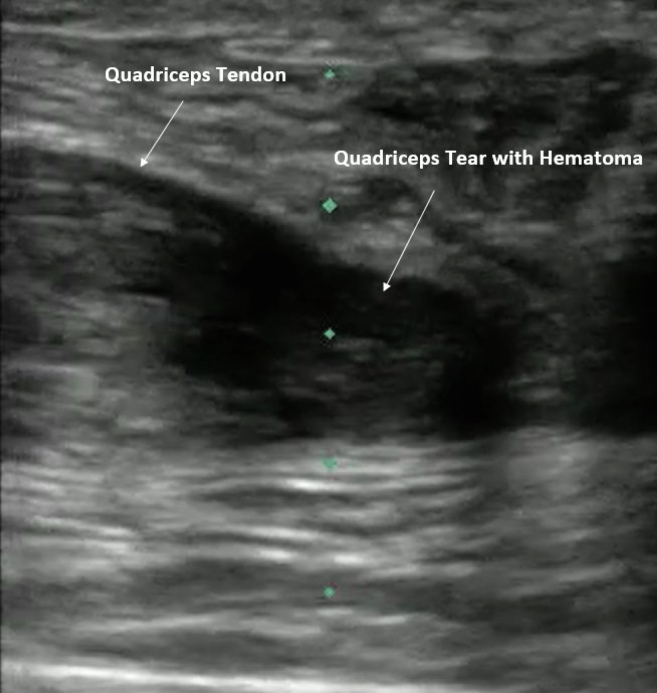

Abstract Image